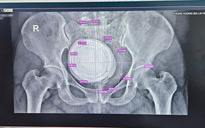

Ông S. nhập viện trong tình trạng tiểu máu tươi kéo dài và sụt cân nhanh. Qua kiểm tra, các bác sĩ phát hiện có khối u bàng quang kích thước lớn (67x52x51mm) xâm lấn sâu, được chẩn đoán là Carcinoma niệu mạc. Bệnh nhân đồng thời mắc bệnh phổi tắc nghẽn mãn tính (COPD) và tăng huyết áp.

Sau khi hội chẩn kỹ, các bác sĩ quyết định phẫu thuật triệt căn tối ưu nhất hiện nay là cắt bàng quang tận gốc kèm chuyển lưu nước tiểu theo phương pháp Bricker.

Thay vì chỉ đưa trực tiếp niệu quản ra da như các kỹ thuật truyền thống trước đây, phương pháp Bricker sử dụng một đoạn hồi tràng (ruột non) của chính bệnh nhân để làm cầu nối dẫn nước tiểu ra ngoài. Kỹ thuật này không chỉ giúp đảm bảo lấy sạch tế bào ung thư mà còn mang lại chất lượng cuộc sống tốt hơn cho người bệnh sau mổ, giảm thiểu các biến chứng về nhiễm trùng và hẹp niệu quản.

Ca mổ thành công sau hơn 6 giờ. Việc ứng dụng công nghệ dao Ligasure hiện đại đã giúp kiểm soát chảy máu tốt trong suốt quá trình bóc tách các mô phức tạp và nạo hạch chậu.